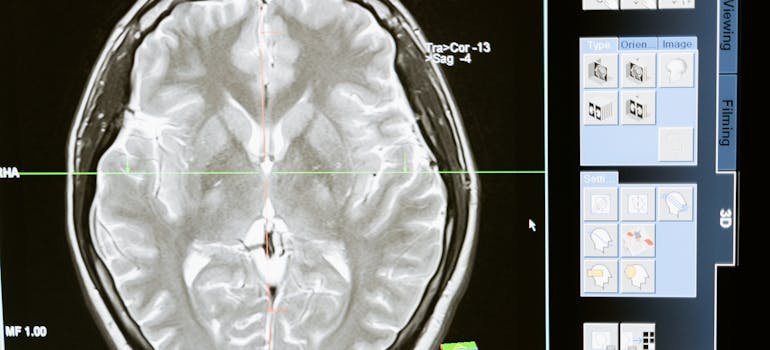

What Effects Does Cocaine Have on the Brain

Cocaine, a potent stimulant, profoundly affects the brain, altering both mood and behavior. When you wonder about what effects does cocaine have on the brain, you need to understand how this substance hijacks the brain’s reward pathways. Cocaine’s influence on the brain is immediate and can be severe, impacting both the structural and chemical frameworks.